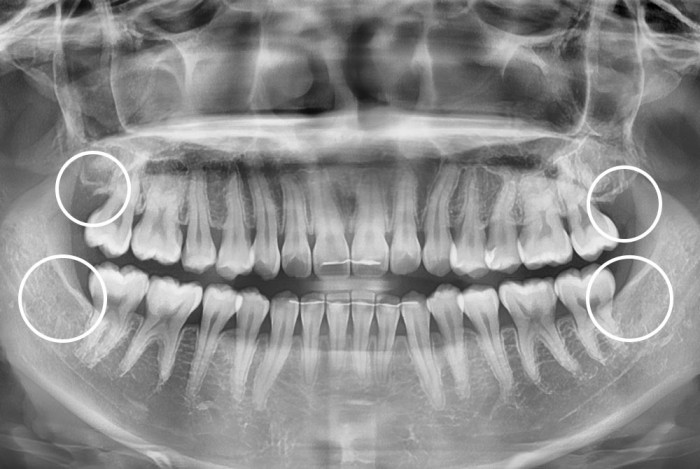

[사랑니] 사랑니

치료후 : 2025-07-08

세종치과는 구강악안면외과학 박사이신 원장님이 발치하는 치과입니다.